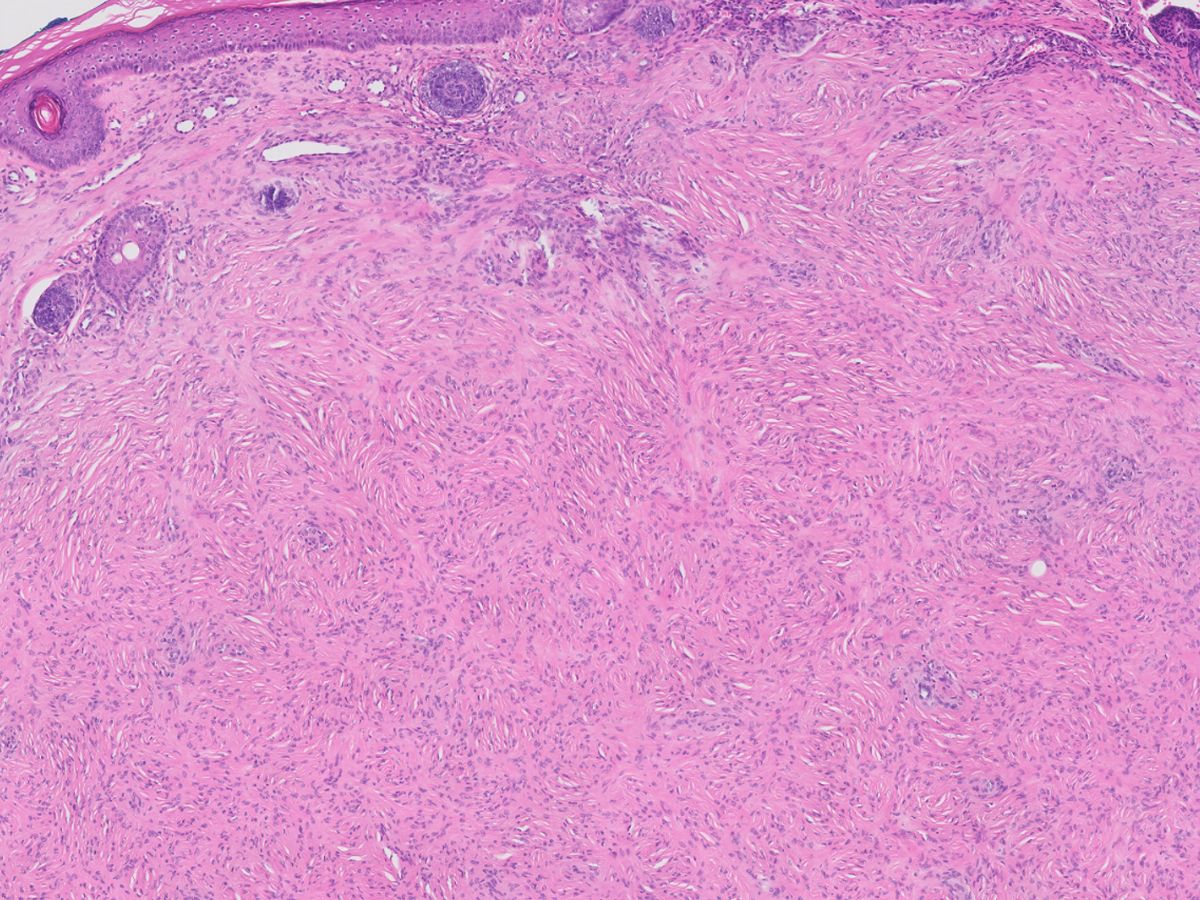

Histologie:Het extraneurale perineurioom (‘soft

tissue perineurioma’) wordt voornamelijk gevonden in weke delen en de huid.

Histopathologisch is er sprake van een vrij scherp begrensde maar niet omkapselde

spoelcellige proliferatie in de dermis en/of subcutis, in een storiform of fasciculair

patroon. Er is sprake van een intraneuraal perineurioom (‘gelokaliseerde hypertrofische

mononeuropathie’) als de perineuriale cellen prolifereren, door het endoneurium

heen groeien en concentrische lagen vormen rondom de fascikels (histologisch

wordt een ‘uienbol aspect’ gezien). Dit kan zich klinisch presenteren als een

vergroting van de zenuw. Vaker wordt dit gezien bij jong volwassenen en kinderen

aan de extremiteiten, even vaak bij mannen als bij vrouwen. Zowel extraneurale

als intraneurale perineuriomen tonen een predominante perineuriale cel differentiatie.

Perineuriomen zijn vaak positief voor EMA en kunnen ook expressie vertonen van

claudin-1, GLUT-1 en CD34. Ze zijn negatief voor S100 en neurofilament.